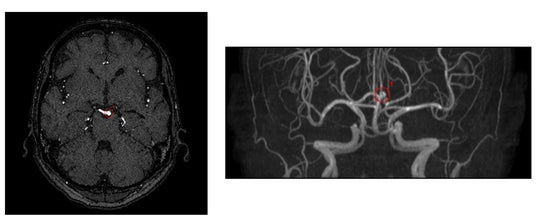

【検出事例】

・旧モデルと比較して「偽陽性」が低減した症例

・脳底動脈の検出事例

※いずれの検出例もイメージであり、実際の製品表示とは異なる場合があります。